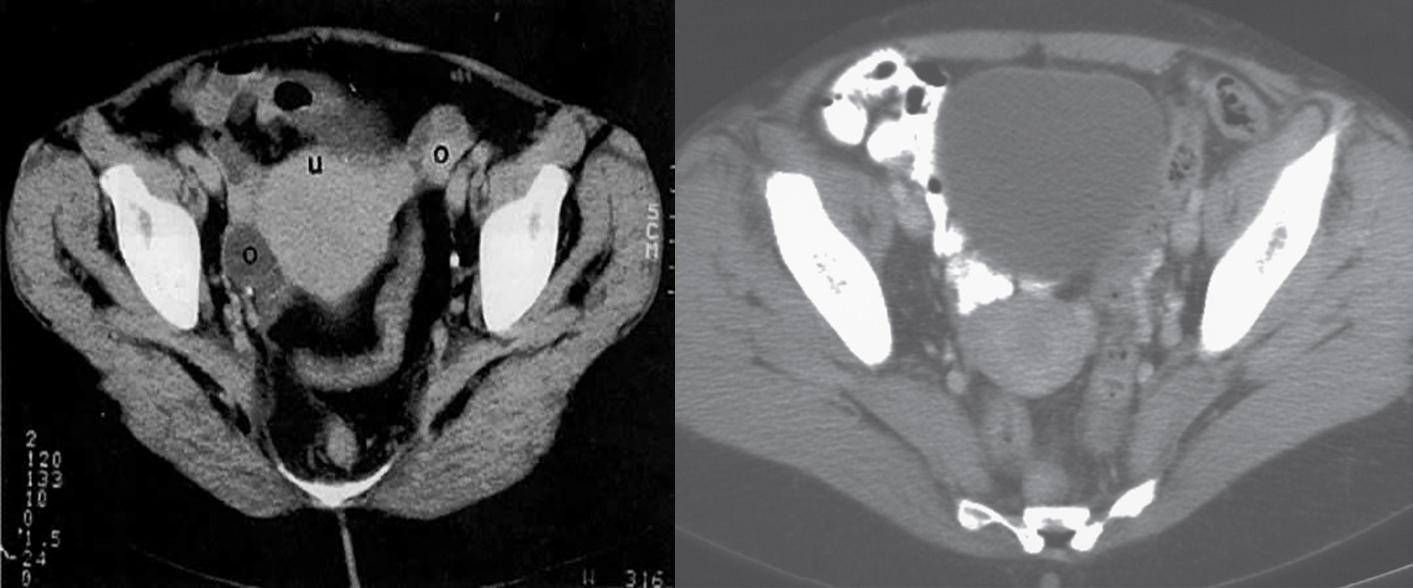

CT image of female pelvis

Normal uterus in a 49-year-old patient, on CT, following intravenous contrast enhancement. Note the oral contrast medium within loops of the small bowel